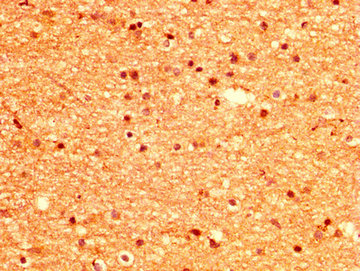

IHC image of CSB-PA015033LA01HU diluted at 1:500 and staining in paraffin-embedded human brain tissue performed on a Leica BondTM system. After dewaxing and hydration, antigen retrieval was mediated by high pressure in a citrate buffer (pH 6.0). Section was blocked with 10% normal goat serum 30min at RT. Then primary antibody (1% BSA) was incubated at 4°C overnight. The primary is detected by a biotinylated secondary antibody and visualized using an HRP conjugated SP system.